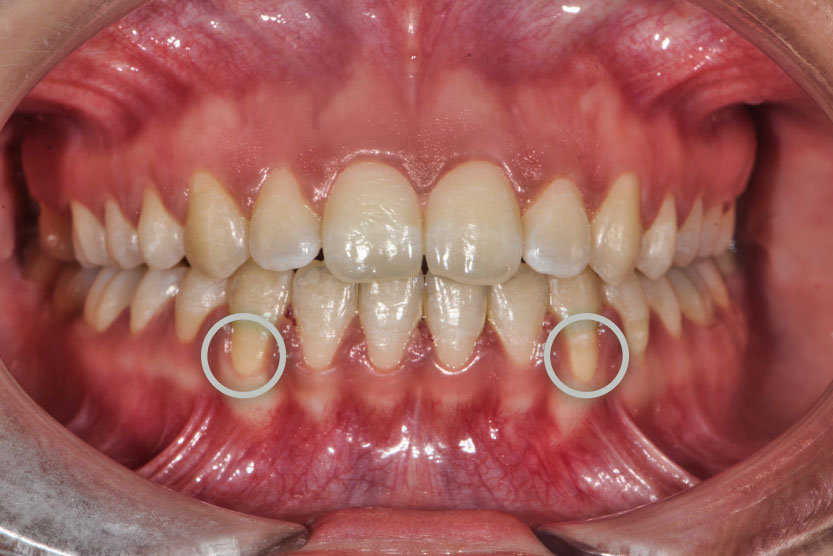

- Periodontitis antes y después (fase clínica): En la fase inicial, el paciente presenta inflamación gingival, sangrado, posible supuración y mal aliento. Tras el tratamiento periodontal, la encía se adapta de forma más estable a la raíz dental, puede apreciarse mayor exposición del diente, pero se recupera la salud de los tejidos y se elimina la infección activa.Periodontitis avanzada antes y después

- Fase ortodóntica:

En casos de pérdida ósea severa es frecuente observar migración patológica, con dientes desplazados y abiertos en abanico. La ortodoncia permite reposicionarlos correctamente, de modo que las fuerzas masticatorias se transmitan de forma más vertical y alineada con el eje del diente, reduciendo el trauma mecánico y contribuyendo a frenar la progresión de la pérdida ósea.